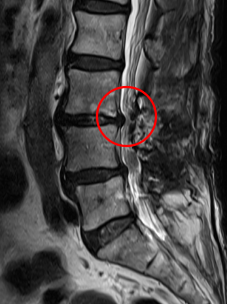

治療後

術後から1か月目の検診時には、左側のお尻の痛みが無くなり、痺れも軽くなったと言っていました。術後のMRI画像でも、しっかりと減圧されていていることを確認しました。しかし切開した箇所が一部癒着不全を起こしていたため、処置を行いました。再縫合から11日目の検診時には、問題なく癒着し、抜糸まで完了しました。